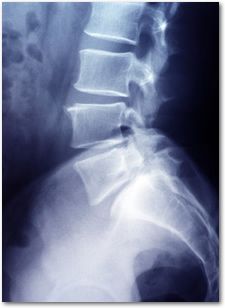

Die Zahl der Personen, welche nach einem Verkehrsunfall über einen Schleudertrauma klagen, nimmt in Deutschland weiter zu. Wo früher Unfallopfer bei Nackenbeschwerden und Muskelverspannung nach einem Verkehrsunfall noch nicht wussten, um was es sich handelt, ist der Begriff Schleudertrauma heutzutage jedem bekannt. Charakteristisch für das Schleudertrauma ist der sogenannte whiplash (Peitschenschlag), wobei insbesondere nach einem Auffahrunfall nach einer Beschleunigung und Überstreckung des Kopfes eine Stauchung der Halswirbelsäule entsteht.Die Höhe des Schmerzensgeldes bemisst sich jedoch nicht nur nach der Dauer der Arbeitsunfähigkeit, sondern auch nach den individuellen Beeinträchtigungen des Geschädigten. So leiden einige Unfallopfer bei einem Schleudertrauma unter erheblichen Muskelverspannungen und sogar Übelkeit und Schwindel. Dies bedeutet, dass man Schmerzensgeldansprüche nicht pauschal festlegen kann, sondern jeden Fall einzeln durch einen Fachmann beurteilen lassen muss.